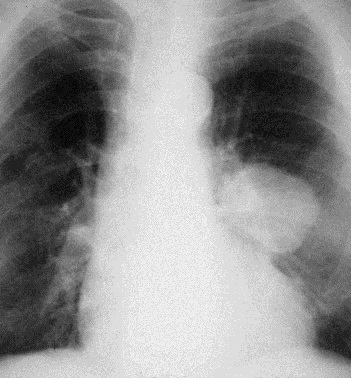

Затемнения могут отображать патологические процессы, поражающие дольку (очаговые тени) (рис. 4), больше чем дольку, но меньше сегмента (фокус затемнения), сегмент или долю (ограниченное затемнение) (рис. 5); большую часть легкого или соответствующей половины грудной клетки (обширное или субтотальное затемнение) (рис. 6). Очаговые тени разделяются на мелкие – до 4 мм в диаметре (поражения ацинуса), средние – 5-10 мм в диаметре (поражения нескольких ацинусов) и большие – 11-15 мм (поражения всей дольки).

Рис. 6. Рентгенограмма органов грудной полости в прямой проекции. Более 2/3 правого легочного поля затемнено. Субтотальное затемнение. Морфологический субстрат – гидроторакс.